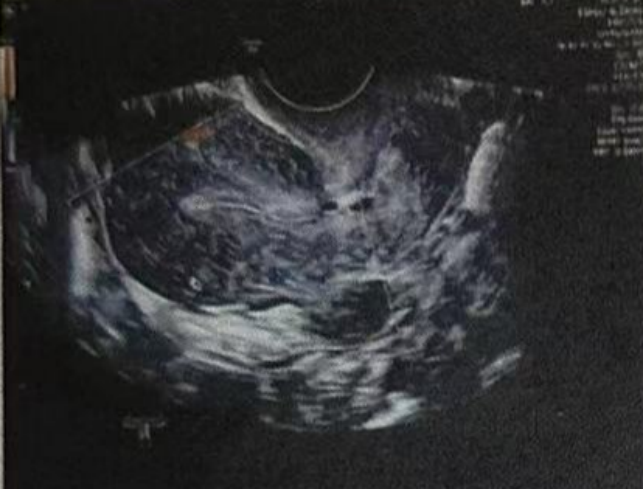

微创清积液

在进行3毫升的子宫峡部切口冲洗后,经过经腹超声检查显示子宫内膜呈三线状,且子宫腔内未见液体。

术后给予抗生素预防感染,为后续胚胎移植扫清子宫环境障碍。

• Pre-Irrigation灌洗前:

• Pre-Irrigation灌洗后: